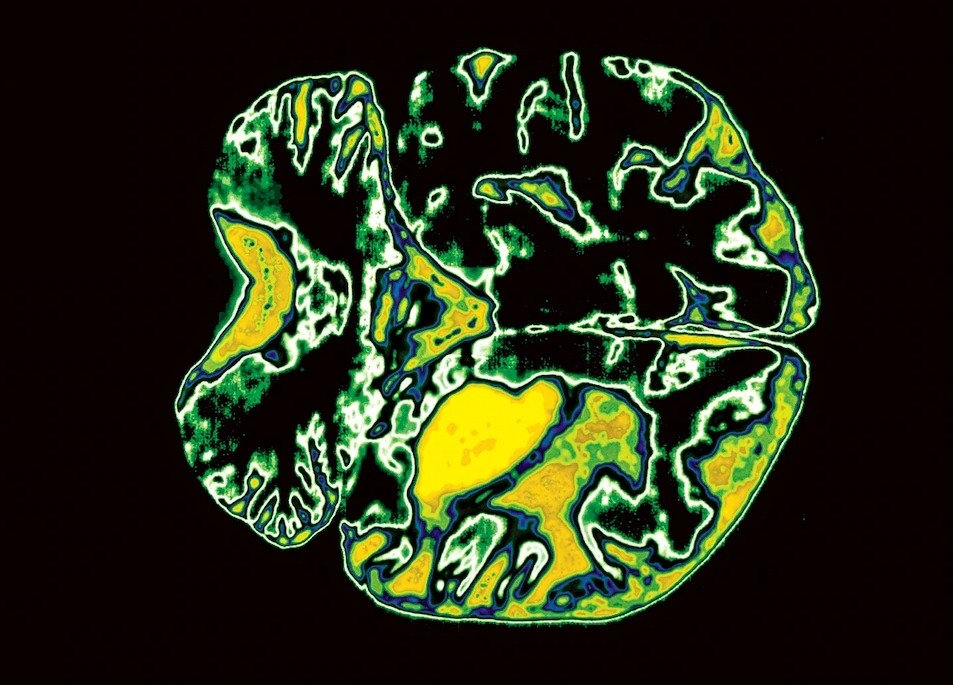

脑部照片。脑部萎缩的迹象,可能是失智的前兆。PHOTOGRAPH BY SCOTT CAMAZINE,SCIENCE SOURCE

老化可怕的部分,就是那些伴随脑部退化而来的失智,还有自我认知的消蚀。但失智并非正常老化的特征。事实上,健康的大脑在老年也运作得很好。就跟身体其他部分一样,脑部组织会因为细胞死亡而有一点点缩小,如果非常非常老的话,脑部会损失大约10%的重量。不过,这样的损失对脑部来说,比其他许多器官的损失更不要紧,因为大脑拥有的细胞比需要的多很多。大脑的神经元也会在细胞死亡时形成新的连接,因为它们的突触是延伸到还活着的细胞上的。有些神经传导物质确实会随着年龄劣化,而大脑的血流也会减少。

这些变动可能会随着时间造成细微的改变。可能会影响短期记忆、语言流利程度和学习能力,但未必会严重影响智力功能。